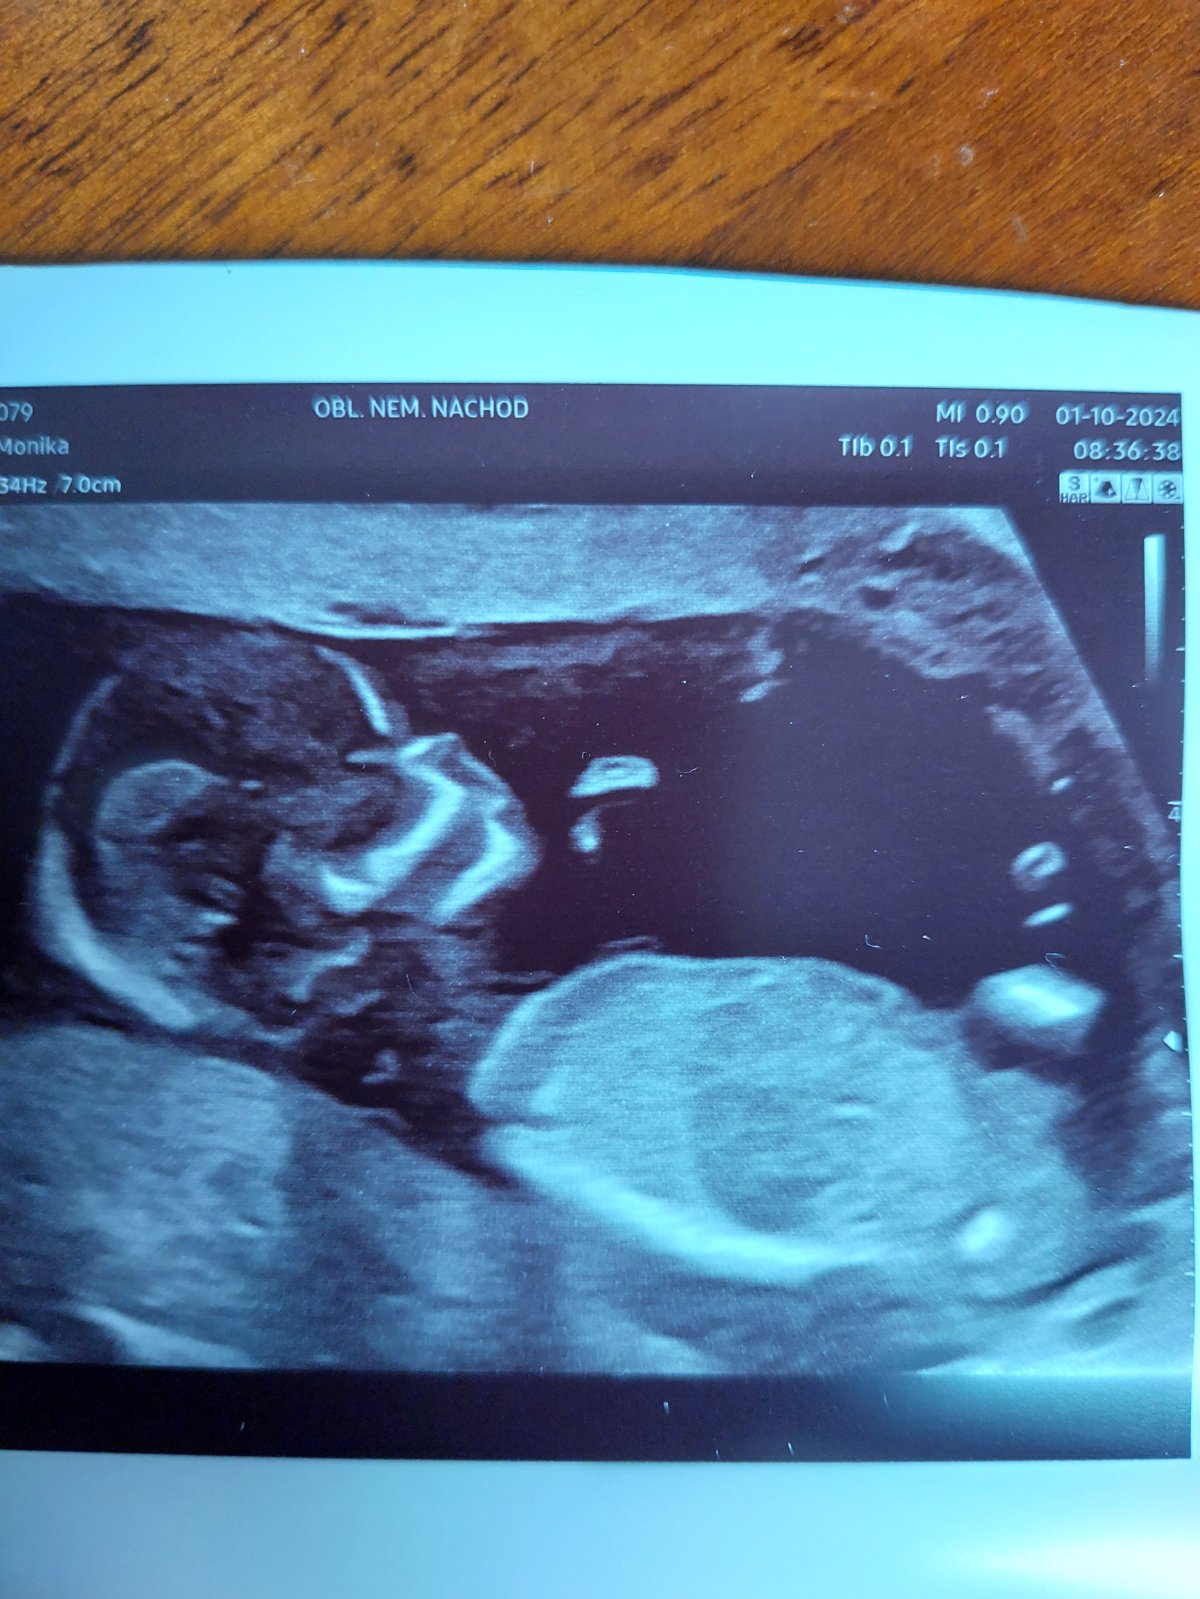

lze z fotky určit pohlaví?

Fotka je z prvotrimestrálního screeningu 13+4tt.